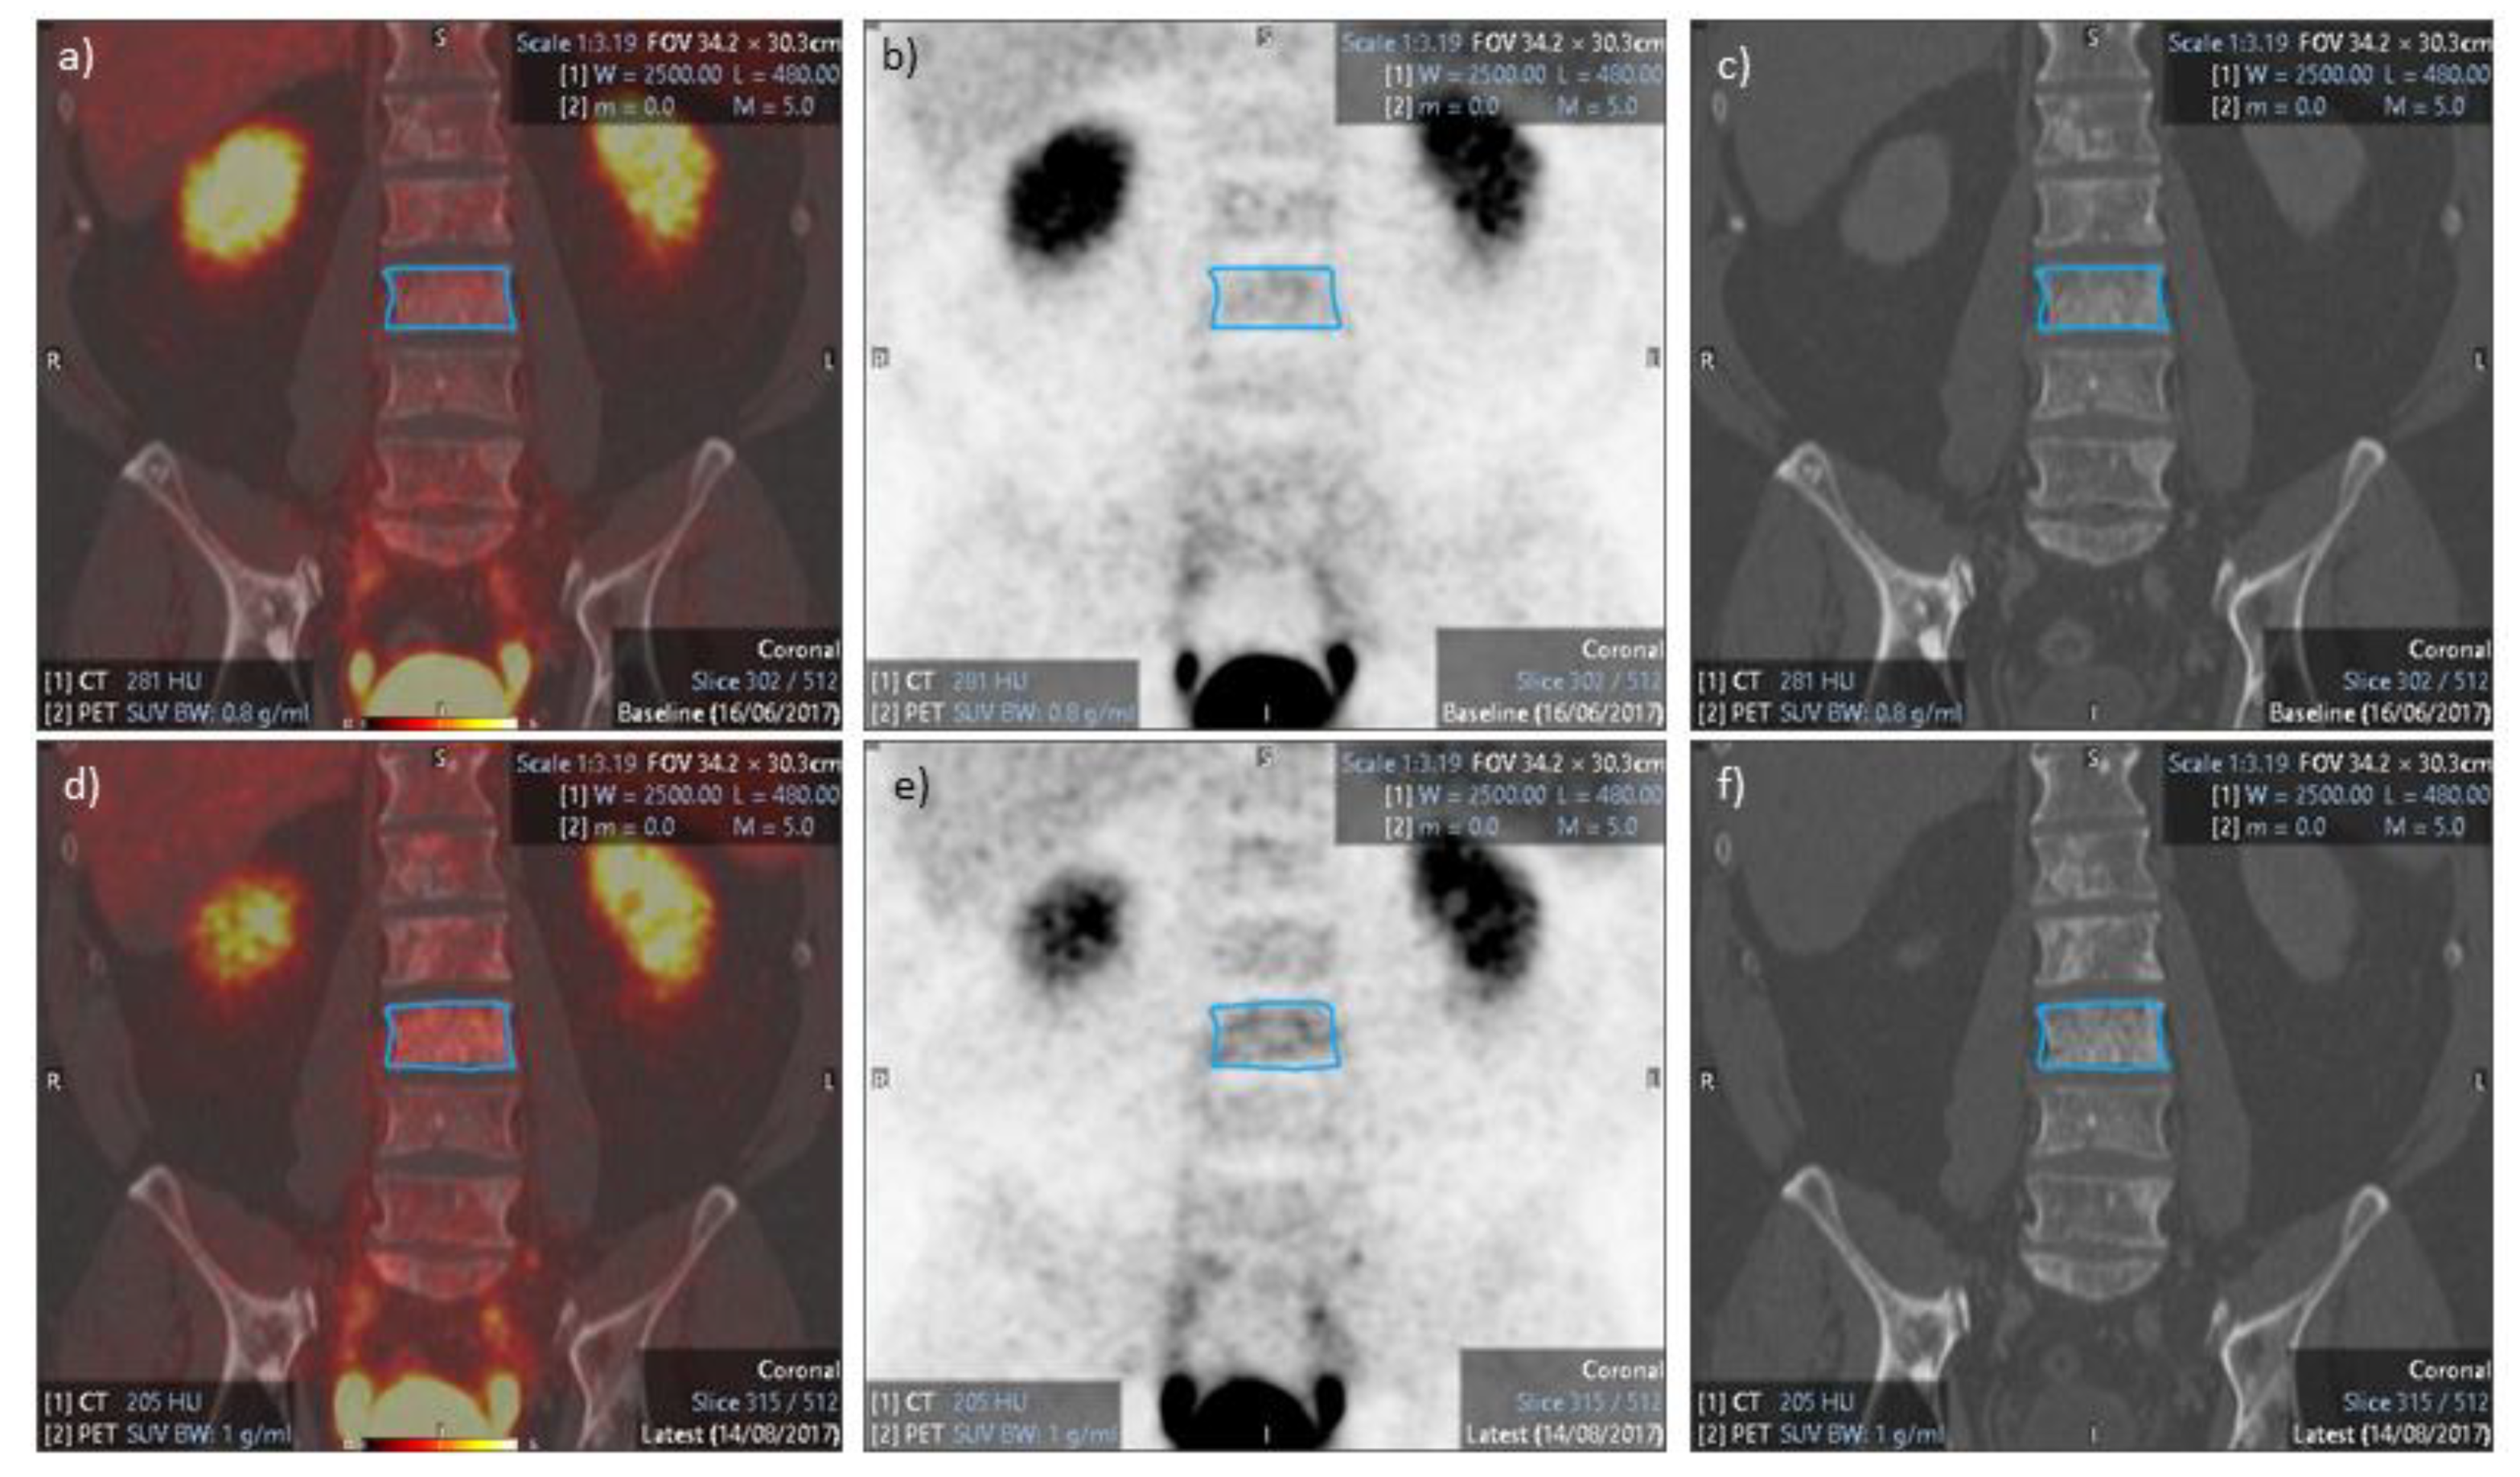

3.1. PET/CT Results